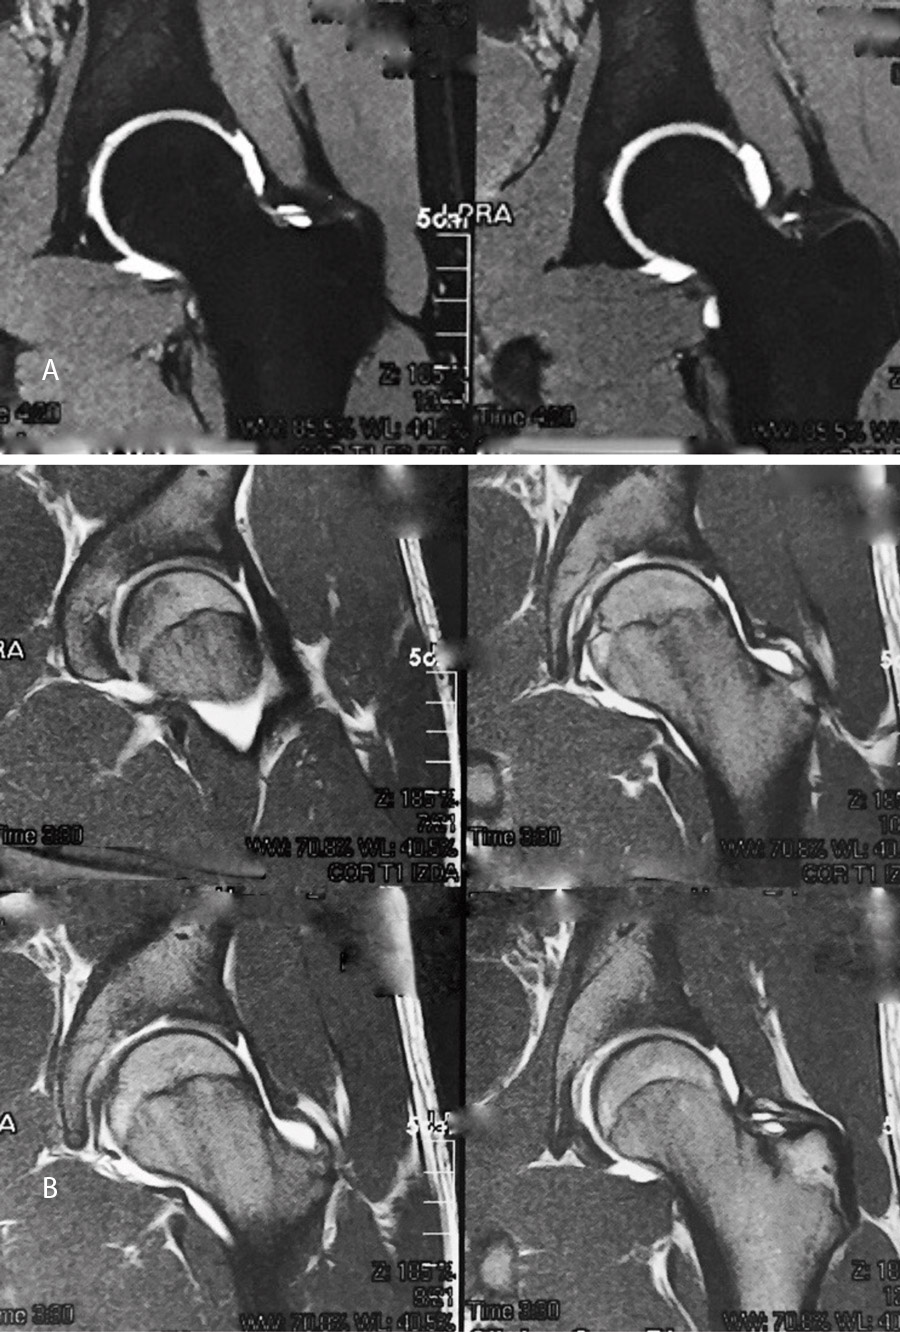

El estudio de imagen mostraba una ausencia de deformidad ósea y no se apreciaron lesiones en la radiografía ni la artrorresonancia (Figuras 1 y 2). El ángulo alfa en la imagen axial izquierda era de 49,6°, mientras que el ángulo de cobertura acetabular de Wiberg era de 34,6°.

Las pruebas de imagen no muestran alteraciones en forma de deformidad de tipo CAM ni PINCER (tanto en radiografías como en resonancia). El ángulo alfa en la proyección axial era de 38,2° y el ángulo Wiberg de 34,5° (Figura 5). Asimismo, el estudio mediante artrorresonancia no evidenció lesiones de labrum ni deformidades del tipo AFA (Figura 6).